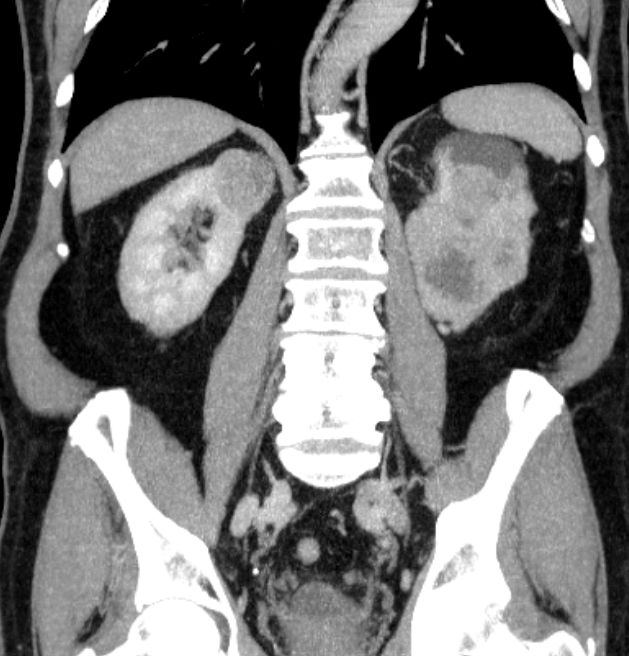

| VHL: 84-98% Veränderung des von Hippel-Lindau-Gens. | 81-jähriger Mann mit einem doppelseitigen Nierenzellkarzinom.![]() |